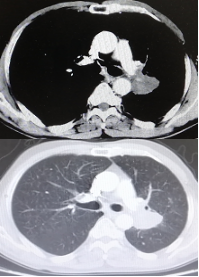

治疗6周期后,左肺病灶明显缩小达58.6%,疗效评估为PR。

CT检查——治疗6周期后

治疗8周期后,左肺病灶较前增加,疗效评估为PD。

CT检查——治疗8周期后